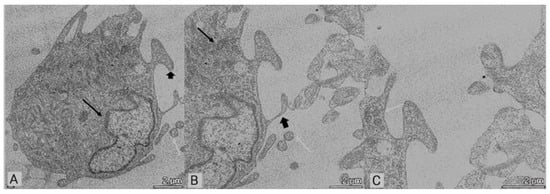

3.2. Transmission Electron Microscopy (TEM)